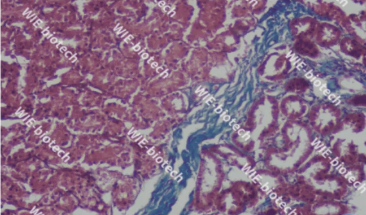

1.Masson三色染色法

用途及原理:称马松染色,经典的结缔组织染色法,用于鉴别胶原纤维和肌纤维。对肝硬化和肝炎导致的纤维增生、肾脏疾病诊断有重要价值。染色原理基于染料分子大小和组织渗透性。淡绿或苯胺蓝分子量大,染色后肌纤维红色,胶原纤维绿色或蓝色,便于区分。